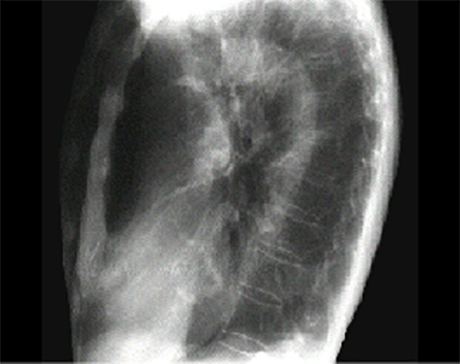

Lateral view

The lateral view is often best for seeing a calcified mitral valve annulus. The J-shaped density is well seen here, as it does not overlap bony structures.